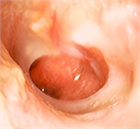

1. 慢性中耳炎の定義:鼓膜穿孔が3か月以上持続し、耳漏を繰り返す中耳の慢性炎症性疾患を指す。世界的には中耳真珠腫を含む概念であることに留意する(推奨度1、RJ)

1. 診断の基本:鼓膜所見による診断が基本であり、必要に応じて側頭骨CTで含気化や陰影を確認する。中耳真珠腫疑い例ではMRIが有用である(推奨度1、RJ)